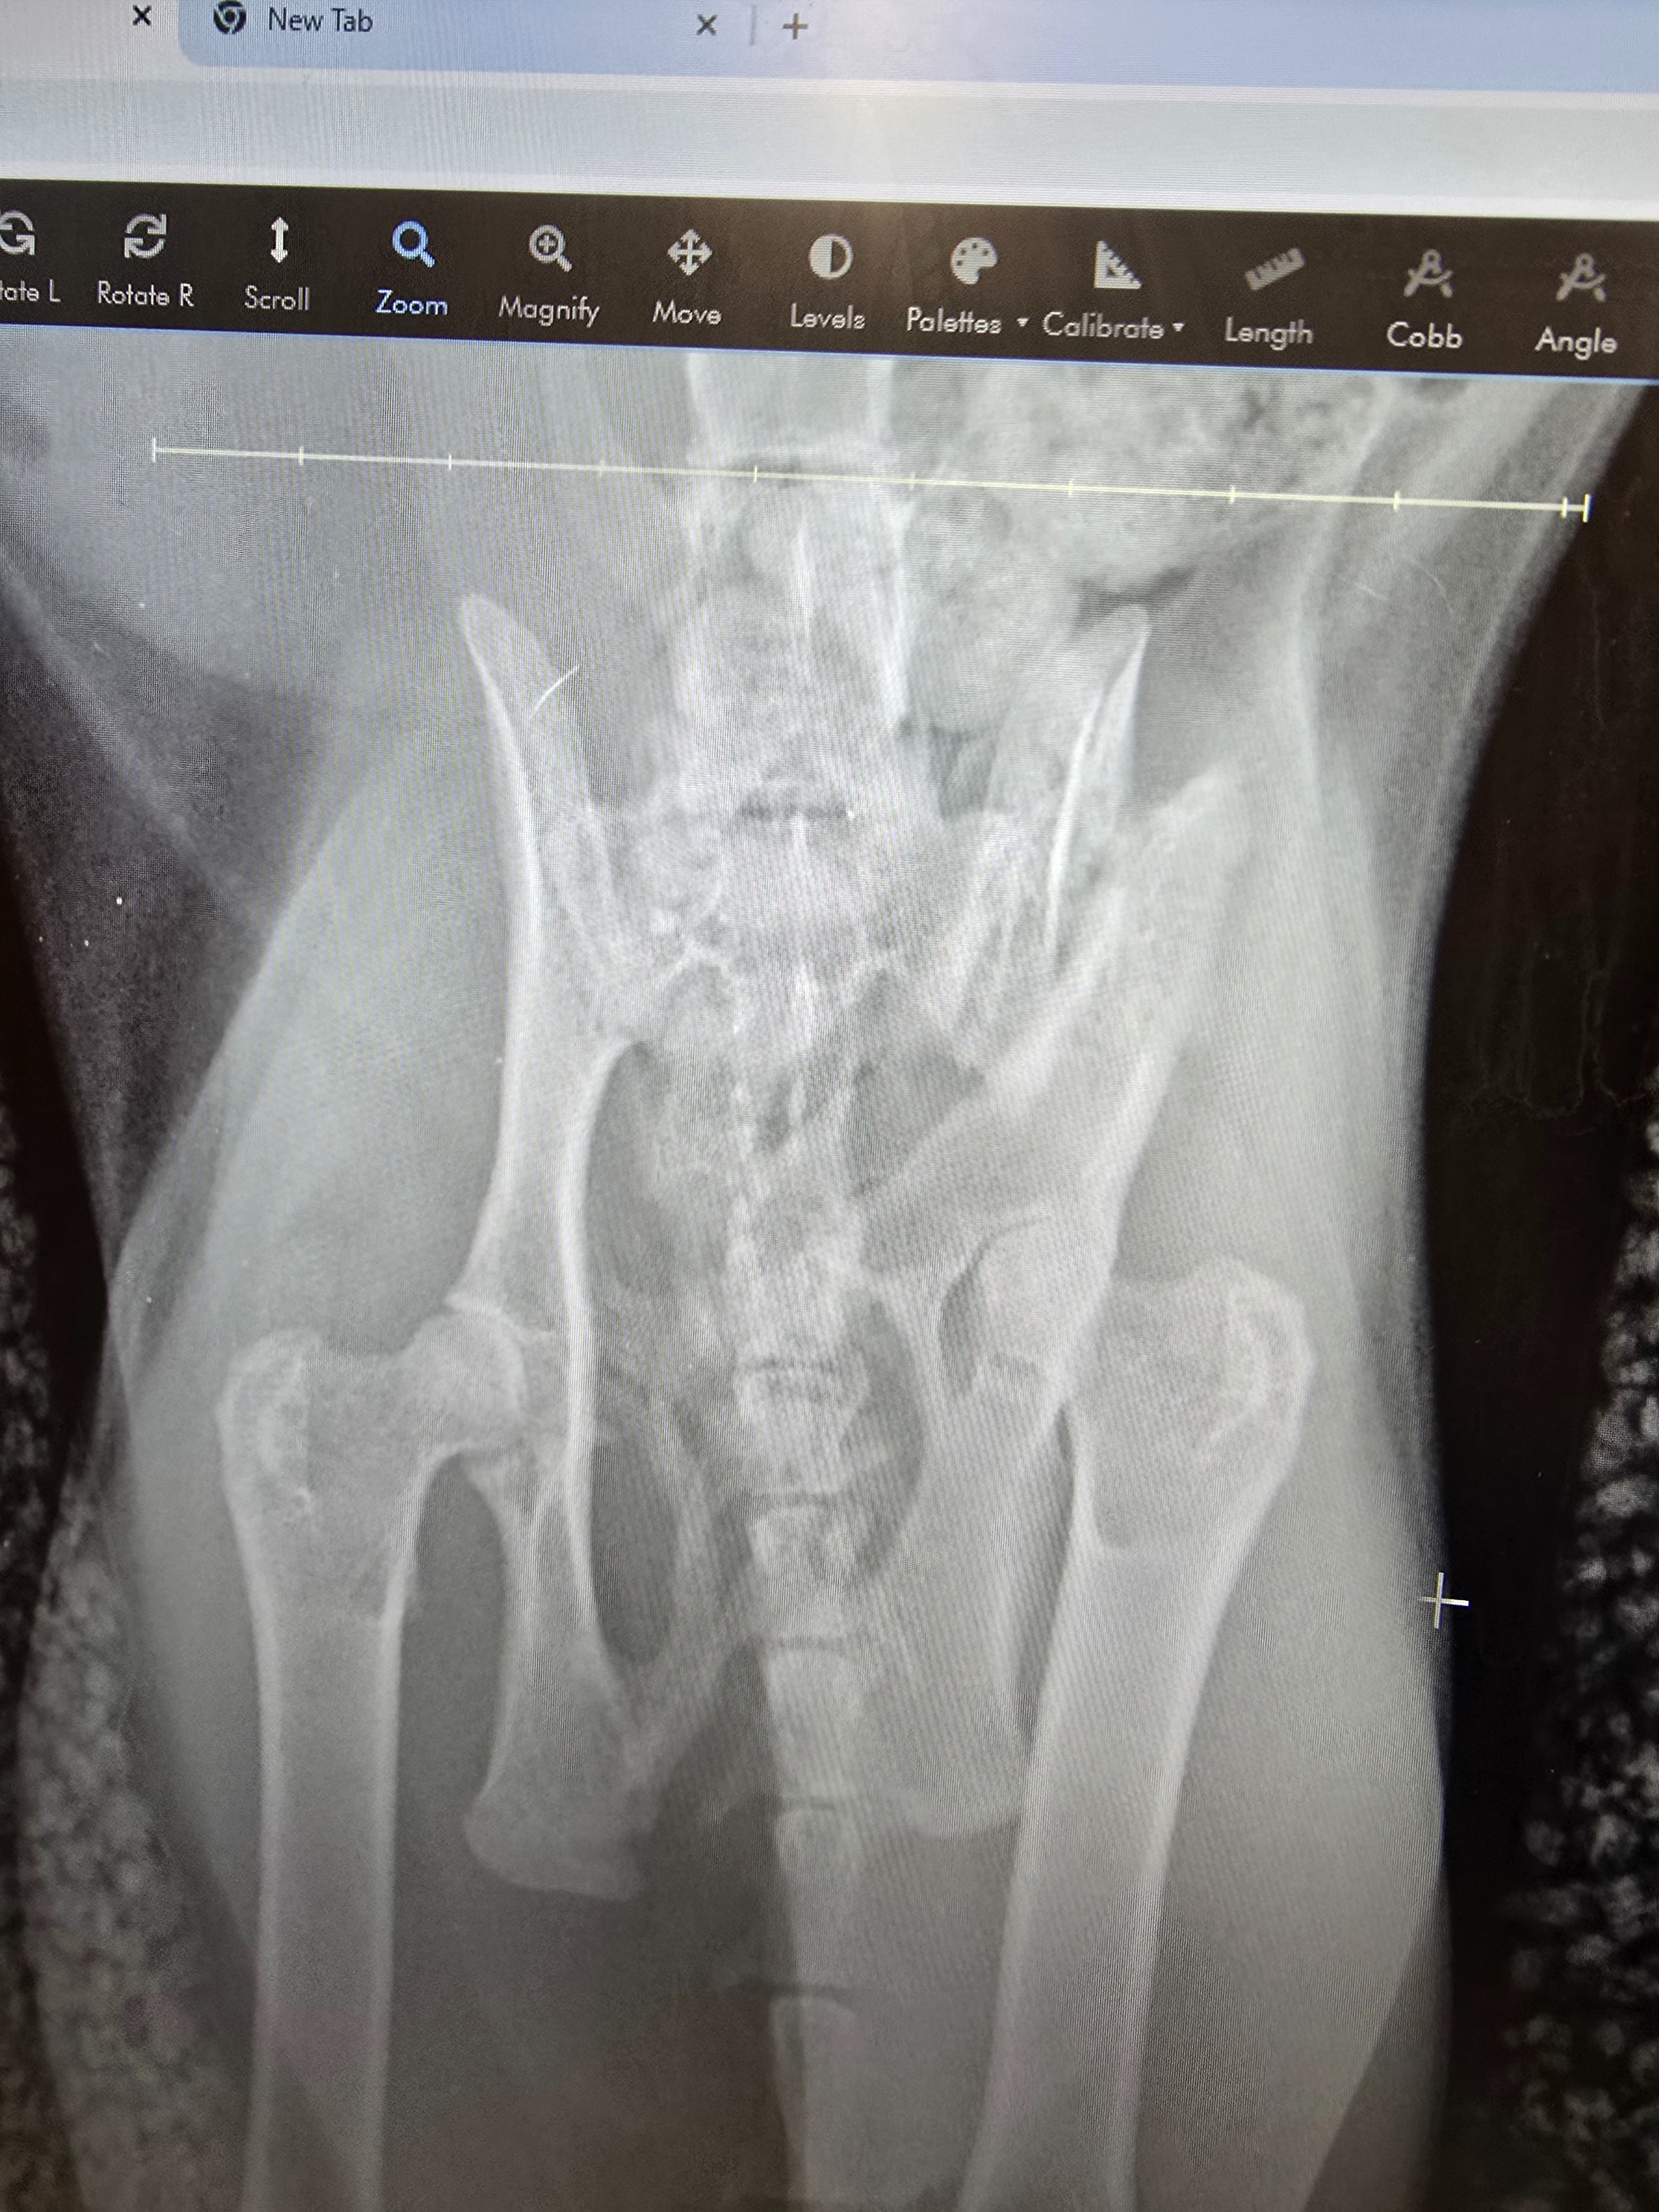

Felix suffered serious injuries, including a dislocated hip and a fractured pelvis.

X-ray images showing the extent of Felix’s injuries